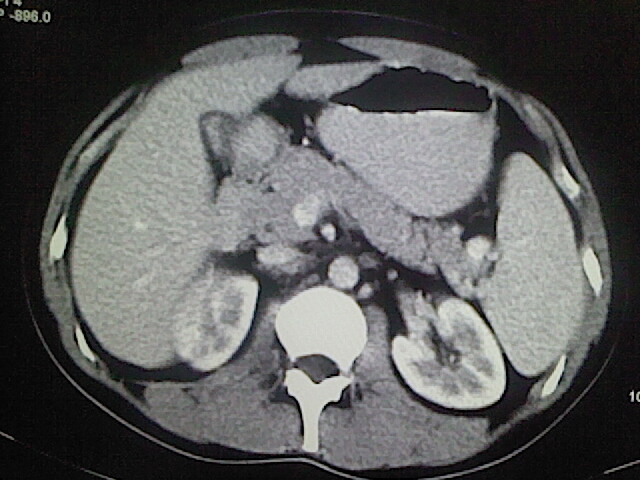

以下是引用卜一在2009-3-14 9:49:00的发言:[br]胆囊萎缩,胆囊壁不规则增厚,内部结构模糊,增强明显强化。另:肝左叶外侧段肝囊肿。支持:慢性胆囊炎!高度可疑:胆囊癌!

以下是引用余辉在2009-3-14 8:48:00的发言:[br]1)慢性胆囊炎。2)肝左叶外侧段肝囊肿。3)脂肪肝。[br]支持,胆囊萎缩,密度增高,不知b超具体有何提示,钙胆汁?结石?

以下是引用jiangjing在2009-3-14 10:18:00的发言:[br]1)慢性胆囊炎。2)肝左叶外侧段肝囊肿。3)脂肪肝。4.】建议行肝功能检查